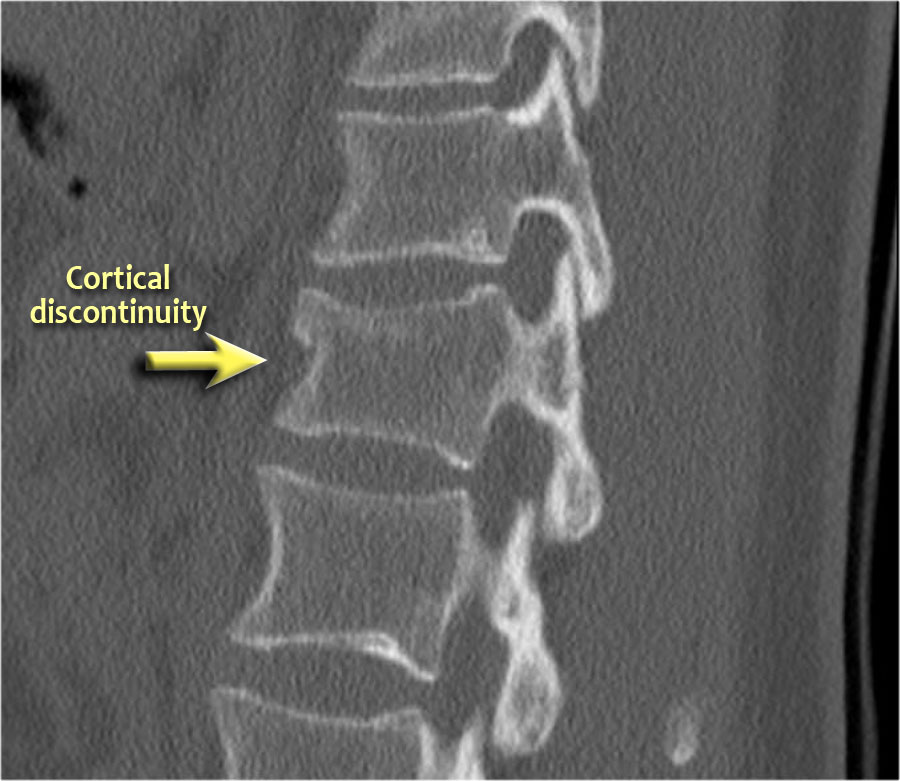

Các hình ảnh là của một bệnh nhân với hình ảnh cột sống tre điển hình do viêm cột sống dính khớp.

Sau khi ngã ngửa, không thấy gãy xương trên phim X-quang.

Tuy nhiên, CT cho thấy một đường gãy mảnh qua mặt trước thân đốt sống và cả qua mỏm gai.

Tiếp tục xem các hình ảnh MRI.